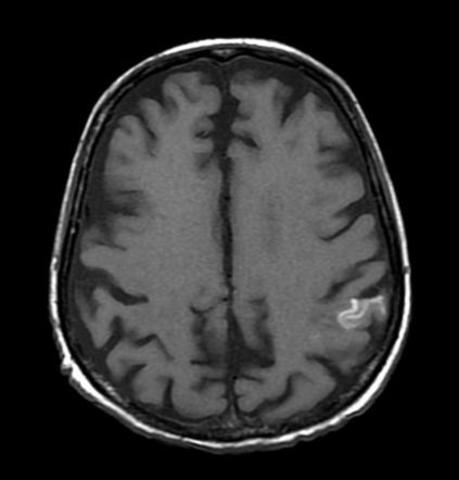

• Lesión hipoxica e isquemica

Lesión hipoxica e isquemica

la disminución de flujo sanguíneo produce isquemia, lo que disminuye el oxigeno provocando una hipoxia, por lo tanto se reduce el metabolismo de glucosa y no se genera suficiente ATP (necesario para el funcionamiento cerebral).

HIPOXIA-ISQUEMIA

Hipoxia: implica la falta de oxígeno con mantenimiento del flujo sanguíneo. (Oxígeno). *Isquemia: reducción muy importante o la ausencia completa de irrigación sanguínea. (Oxígeno, glucosa y eliminación de desechos metabólicos).